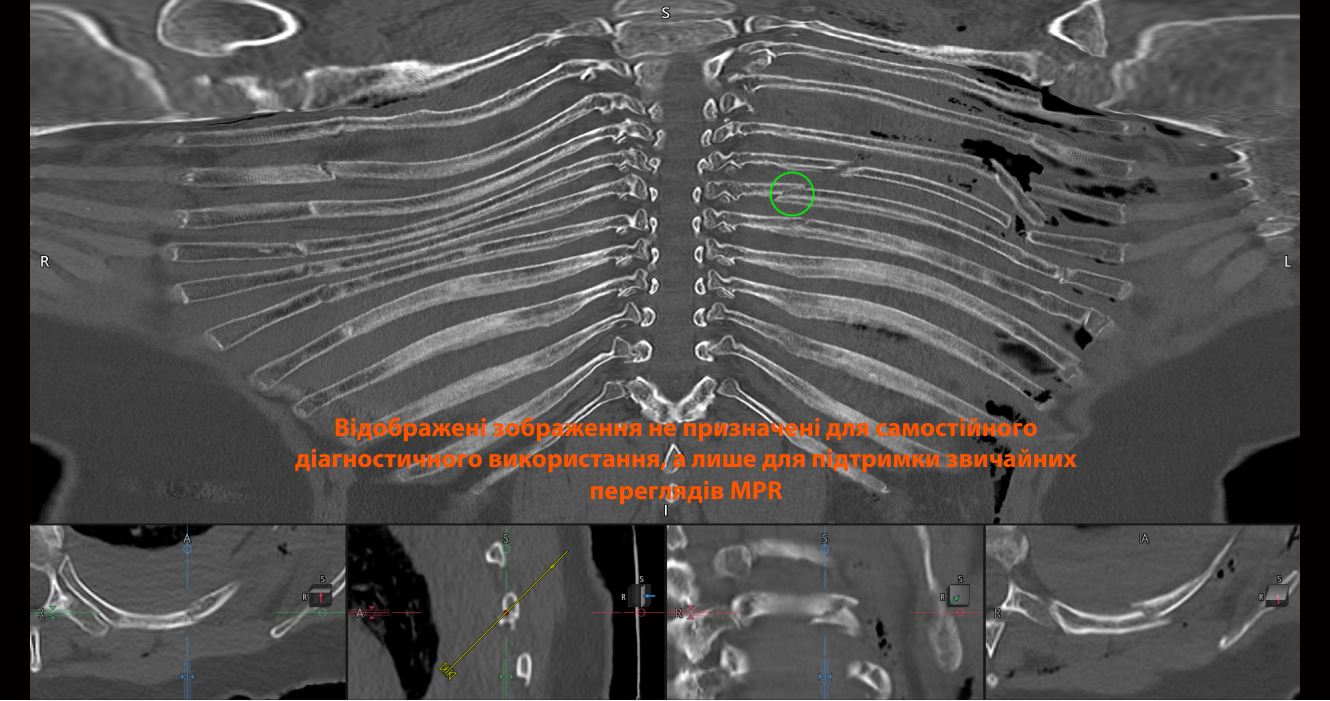

58-річна жінка надійшла до відділення екстреної допомоги після мотоциклетної аварії, і їй було призначено комп'ютерну томографію грудної клітки, живота та тазу. Протокол травми також включав обробку Open Rib, яка автоматично генерує розгорнуте зображення грудної клітки та надсилає цей об'єм безпосередньо до PACS.

Додаток Open Rib забезпечує відкритий вид усіх 12 ребер з обох сторін. З правого боку швидко можна виявити кілька недислокованих переломів ребер з другого по восьме з боку. З лівого боку є один перелом на восьмому ребрі та по два переломи на третьому, четвертому, п'ятому, шостому та сьомому ребрах, що утворює флотуючу грудну клітку — потенційно небезпечний для життя стан.

Додаток Open Rib має три основні автоматичні етапи для отримання розгорнутого безперешкодного зображення грудної клітки. Перший етап — налаштування обмежувального прямокутника для сегментації на основі атласу (A-1). Після розміщення обмежувальних прямокутників виявляється і сегментується кісткова грудна стінка (A-2). Етап розгортання використовує циліндричну проекцію для відображення кісткової грудної стінки на складну корональну площину (A-3). Результатом є розгорнуте безперешкодне 3D-об'єм грудної клітки, показаний в одному зображенні (A-4) та (A-5).

Через кривизну ребер традиційне звітування для оцінки патології ребер вимагає від лікаря постійного перегляду та коригування мультипланарних реконструкцій. Кожне ребро потрібно оцінювати послідовно, одне за одним і з обох боків. Це виснажлива та трудомістка робота. Вид Open Rib має на меті спростити цю задачу, автоматично відображаючи всю грудну клітку в одній площині, щоб допомогти в візуалізації анатомії грудної клітки.. У цього пацієнта вид Open Rib швидко дозволив оцінити кілька дислокованих і недислокованих переломів на кількох ребрах з обох сторін, що призвело до утворення флотуючої грудної клітки з лівого боку.